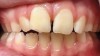

Fig 12. Palatal crib used to passively close bite and break thumb-sucking habit, at delivery (Fig 12), 6 weeks (Fig 13), and 12 weeks (Fig 14).

Figure 12

Fig 13. Palatal crib used to passively close bite and break thumb-sucking habit, at delivery (Fig 12), 6 weeks (Fig 13), and 12 weeks (Fig 14).

Figure 13

Fig 14. Palatal crib used to passively close bite and break thumb-sucking habit, at delivery (Fig 12), 6 weeks (Fig 13), and 12 weeks (Fig 14).

Figure 14

Tongue and thumb pressures also contribute to a high-vaulted palate, which can lead to mouth breathing (Figure 11).31 Additional risks exist for infection and callus development on the thumb. Ideally, the child should quit this habit by age 4, before permanent occlusal changes develop.32 Quitting can be achieved through positive reinforcement and by offering the child comfort during thumb-sucking triggers. The use of bitterants (eg, Mavala Stop, Thum, Control-It!), which are painted on or rubbed into the thumb, is another option.33 A habit breaker appliance may also be utilized if these techniques are unsuccessful. Devices such as a palatal crib, rake, or bluegrass appliance interfere with the thumb and tongue habits and allow the bite to passively close.34 The author recommends utilizing a habit breaker appliance for 6 to 9 months and maintaining reinforcement for a few months once the habit is eliminated (Figure 12 through Figure 14).